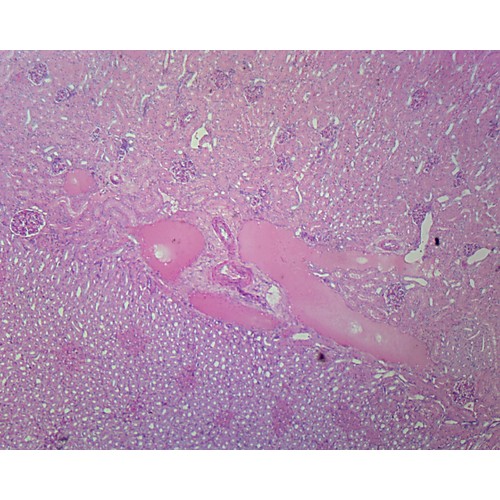

Kidney, TS, H&E stain Microscope slide Southern Biological Microscope Kidney Slides Only a light or electron microscope can reveal these structures. Only a light or electron microscope can. The renal structures that conduct the essential work of the kidney cannot be seen by the naked eye. Histology of connective tissue (capsule, cortex, medulla) in a kidney stained with azan. Understand the electron microscopic view of a proximal and a distal tubule. Microscope Kidney Slides.

Microscopic observations of H&E stained kidney sections (400 × Microscope Kidney Slides Kidney (overall structure) kidneys filter blood and produce urine. Even then, serial sections and computer reconstruction are necessary to give. It describes the internal structures of the kidneys including the cortex, medulla, renal pyramids, and nephrons. Histology of connective tissue (capsule, cortex, medulla) in a kidney stained with azan. Only a light or electron microscope can. In this virtual slide. Microscope Kidney Slides.